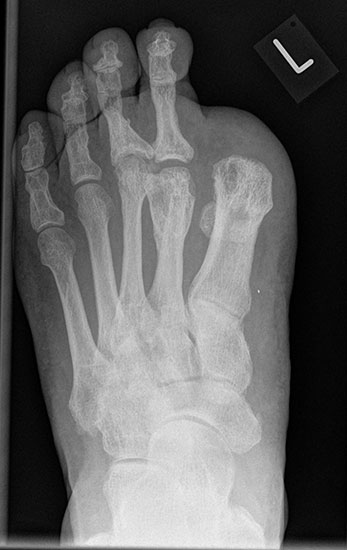

Es ist ungünstig, wenn wenige Kleinzehen lateral belassen werden. Das führt zum Kippen der Nachbarzehen oder zur Fehlstellung der verbliebenen Zehen (Abb. 18 - 20) und schließt eine optimale schuhtechnische Versorgung aus. Weitere Druckulzera sind zu erwarten. Die Großzehe kann als einzige Zehe belassen werden, wobei dann bisweilen die Arthrodese im Großzehengrundgelenk zur Stabilisierung ratsam ist (Abb. 21, 22).